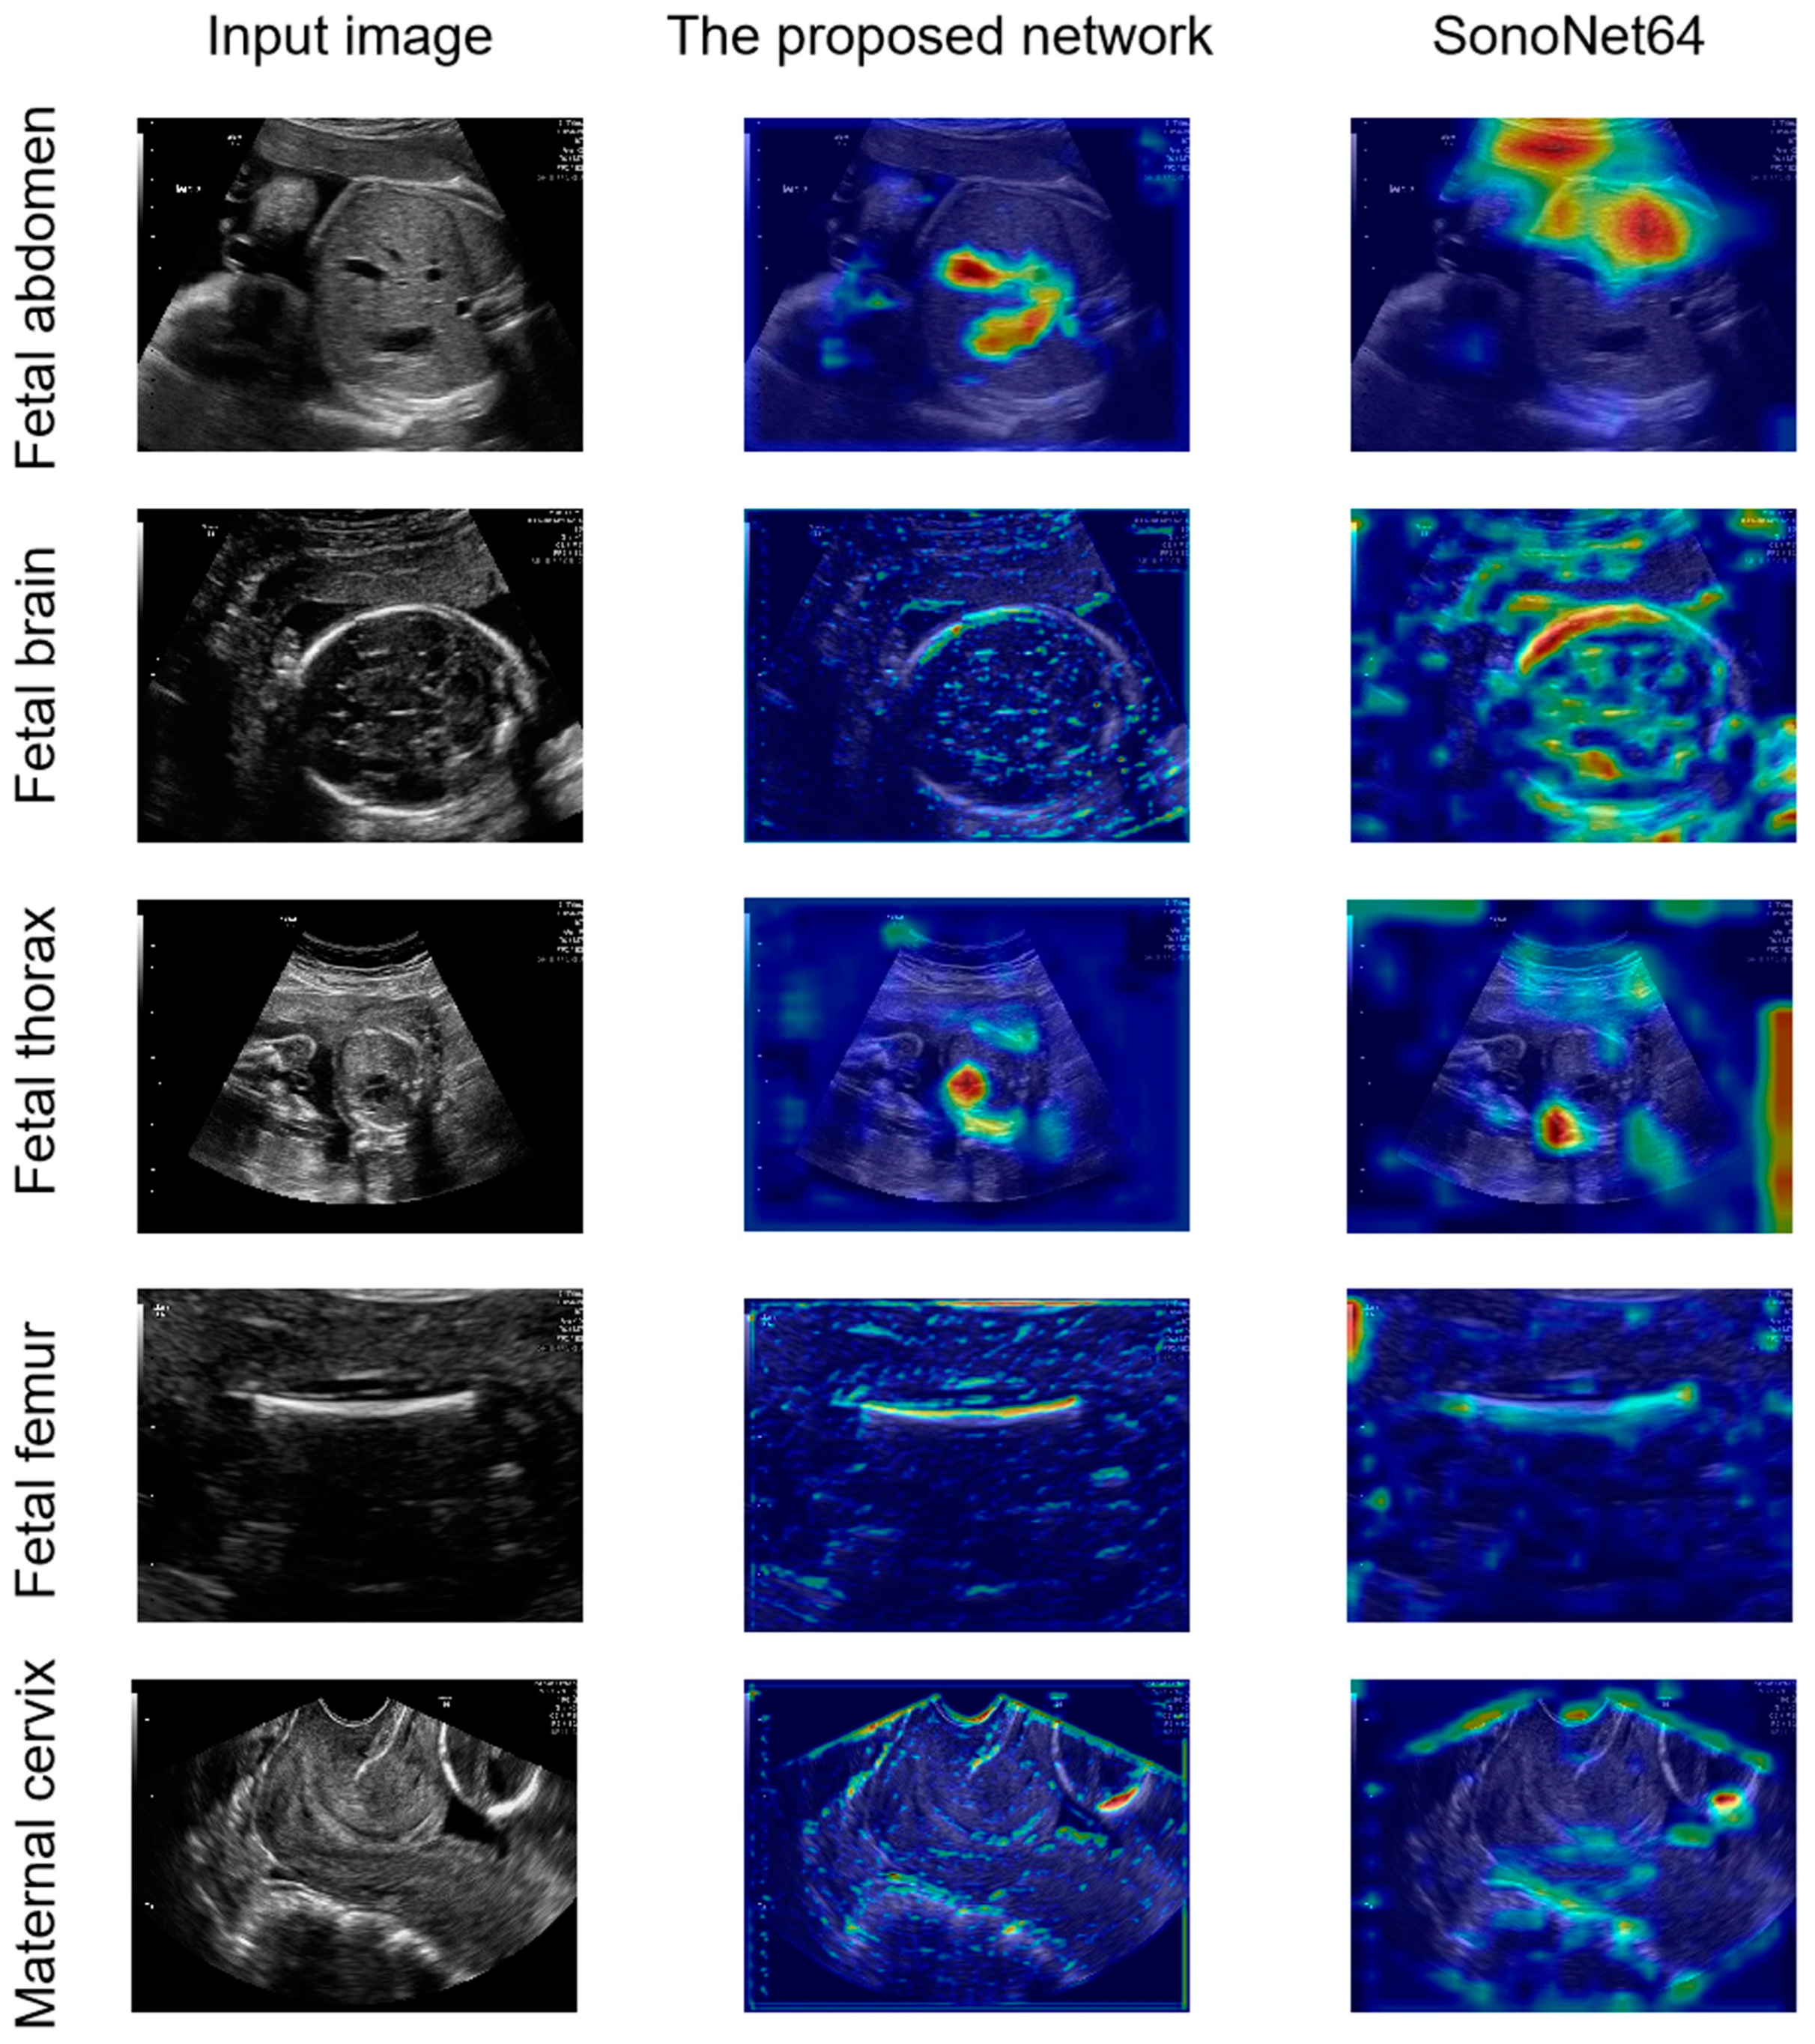

Compared with SonoNet64, the proposed network had a better ability in the detection of the fetal abdomen and fetal thorax standard planes (Figure 4 and Figure 5). To explore the interpretability of the proposed LPC-SonoNet and SonoNet64, the gradient-weighted class activation mapping (GradCAM) [34] technique was used, and the heatmaps generated with GradCAM which used warm color to depict the attention of the network on the input data are shown in Figure 6. The heatmaps of LPC-SonoNet are more concentrated in the relevant regions of the fetal abdomen and fetal thorax standard planes than SonoNet64. It is possible that the pyramid architecture in LPC blocks enable the proposed network to have a large receptive field so that it can focus on the right regions related to the class of standard plane. However, this architecture makes the proposed network ignore the boundary of tissue so that the proposed network performed worse than SonoNet64 in the detection of the outlines of the skull and femur which is important in the classification of brain and femur standard planes.

Figure 6.

The comparison of heatmaps from the proposed network and SonoNet generated by the gradient-weighted class activation mapping (GradCAM) [34] technique.